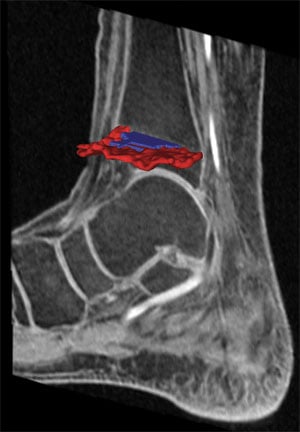

HSS scientists and clinicians developed a new technique for obtaining images of growth plate injuries in children can now help guide treatment decisions. The technique provides computer-generated 3D models obtained from MRIs that surgeons can use in the operating suite to achieve optimal results.

3D models of growth plate injuries obtained from MRIs offer greater precision and speed with less radiation than CT imaging.